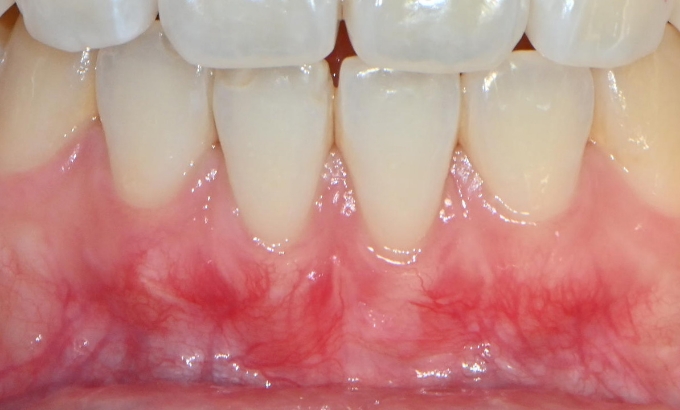

선천적으로 얇은 잇몸, 잇몸의 두께를 고려하지 않은 교정 치료, 잇몸의 염증 등으로 인해 잇몸이 퇴축하여 치아 뿌리가 드러난 경우에는 치아의 길이 가 길어 보이며 치아 수명이 줄어들어 시린 증상이 발생하기도 합니다. 노출된 치아 뿌리 위에 잇몸을 이식하여 잇몸이 퇴축하기 전의 상태로 회복시키는 시술입니다.

선천적으로 얇은 잇몸, 잇몸의 두께를 고려하지 않은 교정 치료, 잇몸의 염증 등으로 인해 잇몸이 퇴축하여 치아 뿌리가 드러난 경우에는 치아의 길이가 길어 보이며 치아 수명이 줄어들어 시린 증상이 발생하기도 합니다. 노출된 치아 뿌리 위에 잇몸을 이식하여 잇몸이 퇴축하기 전의 상태로 회복시키는 시술입니다.

교정 치료 후 아래 앞니 각도 이상으로 인해 발생한

잇몸 퇴축, 부분 교정을 통한 각도 수정을 동반한 증례